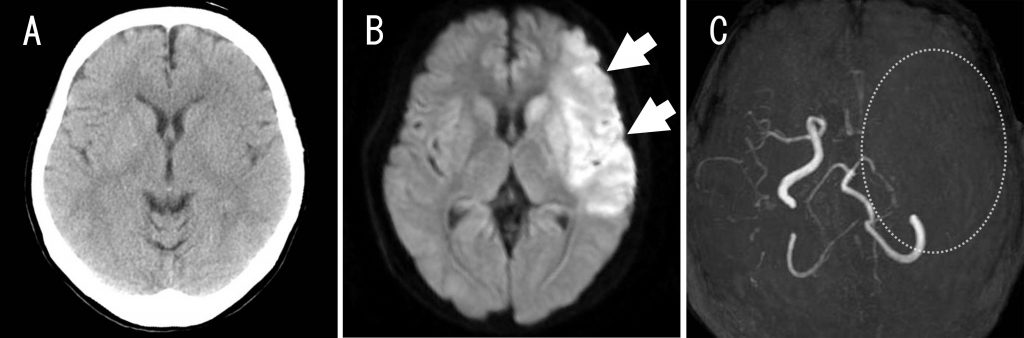

心窩部痛にて発症した気管支動脈蔓状血管腫の1例(A case of racemose